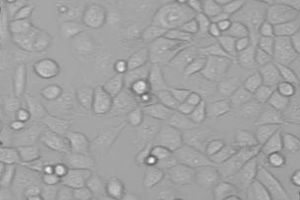

Scientists used cells taken from human tumours and looked at the effect of blocking each of these two energy sources in turn.